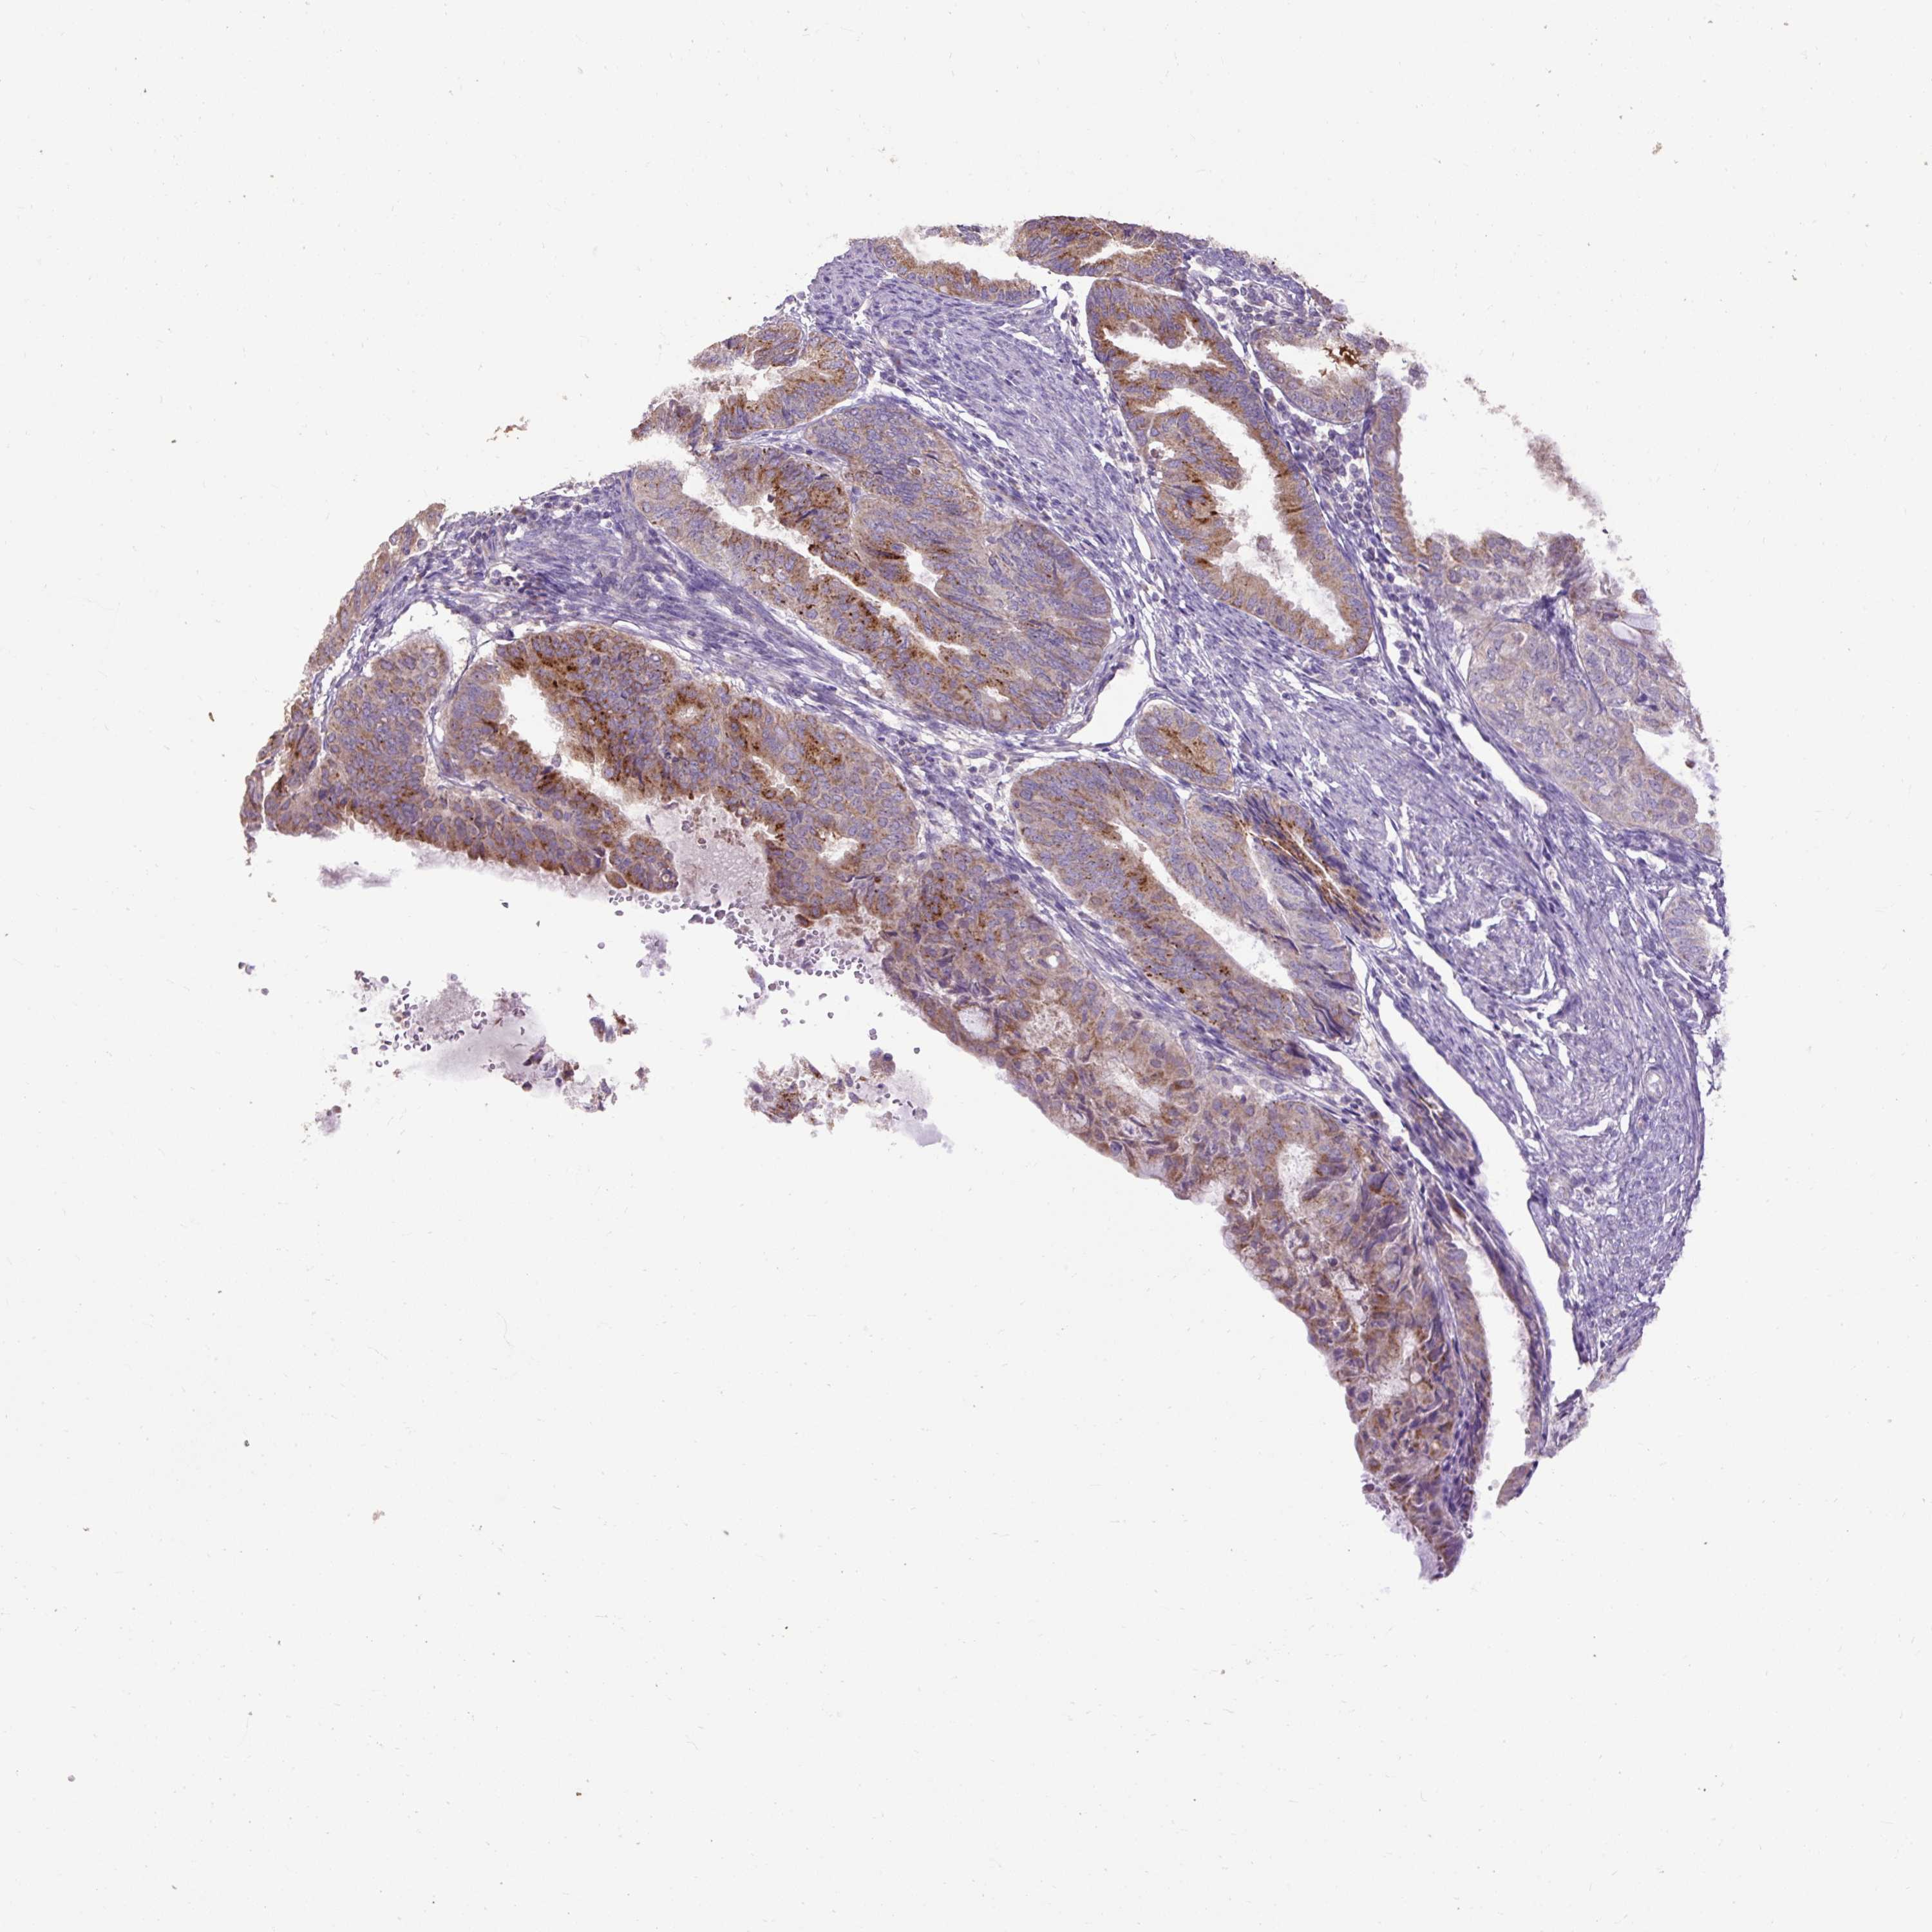

ENDOMETRIAL CANCER - Protein expressioni

A mouse-over function shows sample information and annotation data. Click on an image to view it in a full screen mode. Samples can be filtered based on level of antibody staining by selecting one or several of the following categories: high, medium, low and not detected. The assay and annotation is described here.

Note that samples used for immunohistochemistry by the Human Protein Atlas do not correspond to samples in the TCGA dataset.

Antibody stainingi

Antibody staining in the annotated cell types in the current human tissue is reported as not detected, low, medium, or high, based on conventional immunohistochemistry profiling in selected tissues. This score is based on the combination of the staining intensity and fraction of stained cells.

Each image is clickable and will lead to virtual microscopy that enables deeper exploration of all samples and also displays staining intensity scores, fraction scores and subcellular localization as well as patient and tissue information for each sample.

Antibody HPA054824

Staining

High

Medium

Low

Not detected

Intensity

Strong

Moderate

Weak

Negative

Quantity

>75%

75%-25%

<25%

None

Location

Nuclear

Cytoplasmic/membranous

Cytoplasmic/membranous,nuclear

Adenocarcinoma, NOS